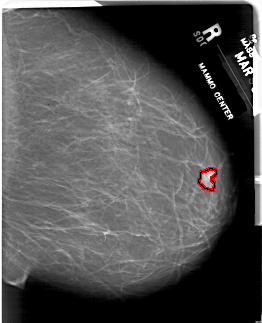

A_1815_1.RIGHT_MLO

RIGHT_MLO LINES 6121 PIXELS_PER_LINE 4966 BITS_PER_PIXEL 12 RESOLUTION 43.5 OVERLAY

FILE: A_1815_1.RIGHT_MLO.OVERLAY

TOTAL_ABNORMALITIES 1

ABNORMALITY 1

LESION_TYPE MASS SHAPE TUBULAR MARGINS CIRCUMSCRIBED

ASSESSMENT 4

SUBTLETY 4

PATHOLOGY BENIGN

TOTAL_OUTLINES 1

BOUNDARY